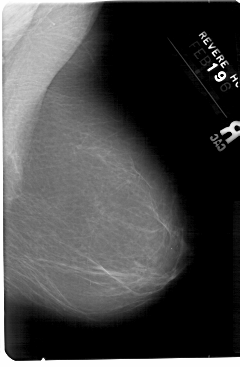

A_1346_1.RIGHT_CC

RIGHT_MLO LINES 5491 PIXELS_PER_LINE 3586 BITS_PER_PIXEL 12 RESOLUTION 43.5 NON_OVERLAY